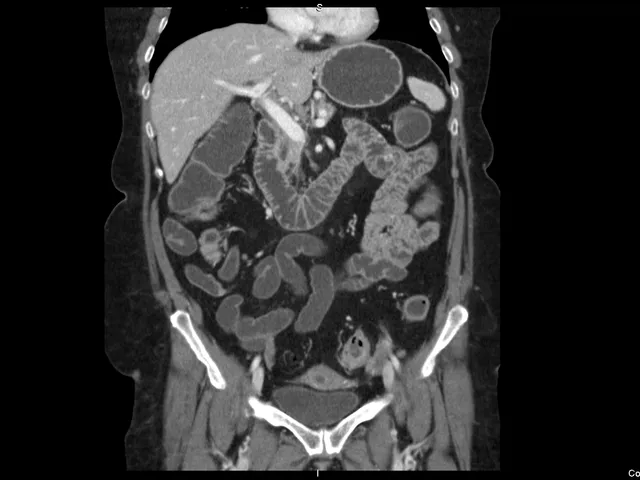

Working in the on-call section of Telemedicine Clinic exposes our on-call team members to a high concentration of acute abdominal pathologies. Whilst presentation of peritonitic patients can sometimes be atypical and challenging at presentation in the ER, the radiological assessment of the CT studies obtained in this group of patients can often be challenging as well.

Based upon experiences learned in our daily emergency work, a step-by-step assessment is proposed to facilitate radiology readings. In this programme participants are exposed to a wide variety of commonly and less commonly encountered acute bowel conditions.

- To obtain extensive overview of intestinal emergencies, including inflammatory (common and less common) conditions, obstruction, ischemia, acute presentation of malignancy and others.

- To gain experience in step-by-step analysis of imaging features commonly encountered in the bowel, including (but not limited to) luminal width, wall thickness, density and enhancement. This in the ends facilitates the design of the differential diagnosis in most cases.